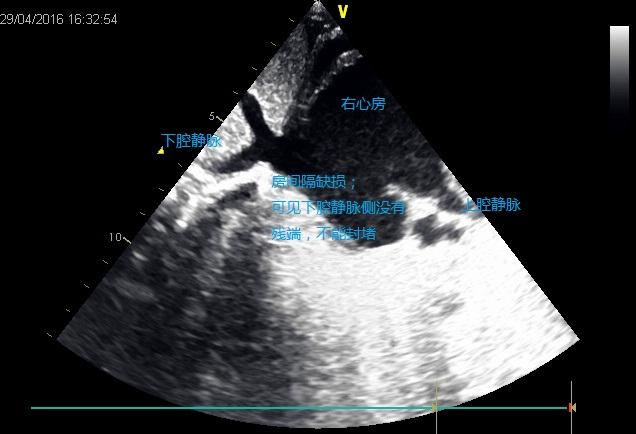

房间隔缺损(上腔型,腔静脉型房间隔缺损经胸超声心动图分型困难)

图片尺寸400x300